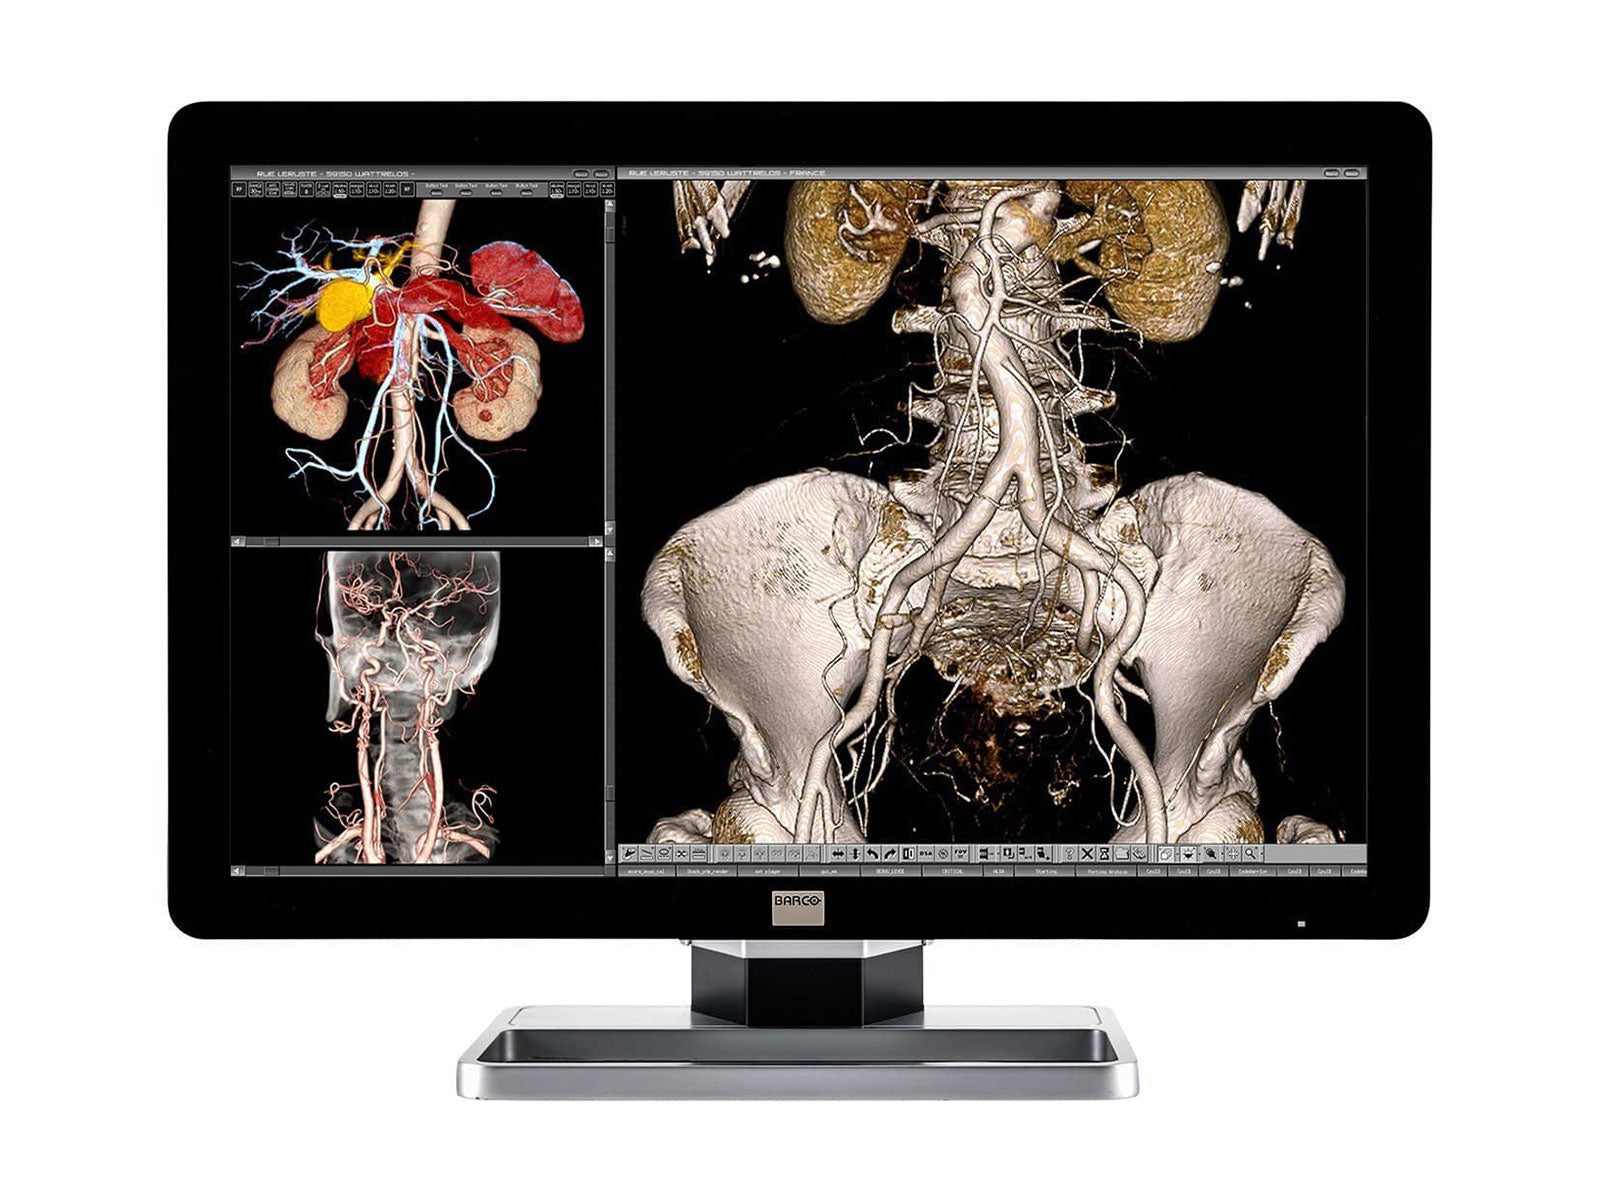

Barco Coronis Fusion MDCC-6430 6MP 30" Color LED General Radiology PACS Display

Barco Coronis Fusion MDCC-6530 6MP 30" Color Medical Diagnostic Radiology Monitor

Barco Coronis Fusion MDCC-6330 6MP 30" Color LED General Radiology PACS Display

Barco Coronis Fusion MDCC-6230 6MP 30" Color LED General Radiology PACS Display

Complete PACS General Radiology Station | Barco 6MP MDCC-6230 Display | HP Workstation | Dictation Mic | Worklist Monitor (6230Z4R)

Complete PACS General Radiology Reading Station | Barco 6MP MDCC-6430 | HP Workstation | Dictation Mic | 24" Worklist Monitors (6430Z4R)

Complete PACS General Radiology Station | Barco Coronis MDCC-6330 6MP Color LED Display | HP Workstation | Dictation Mic | Worklist Monitor (6330Z4R)

Complete PACS General Radiology Station | Barco Coronis MDCC-6430 6MP Color LED Display | HP Z4 G5 Workstation | Dictation Mic | Worklist Monitor (6430Z4G5)